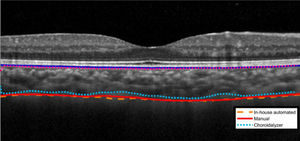

Fig. 6 presents the Bland-Altman analysis comparing the in-house automated method and the open-source automated method, the Choroidalyzer, to manual segmentation. The mean difference (± standard deviation) between the manual and the in-house automated methods was 1.75 ± 18.52 µm for the 1-mm region and −0.07 ± 17.45 µm for the 3-mm region. In contrast, the Choroidalyzer consistently underestimated choroidal thickness in both regions compared to the manual method, with a mean difference of −39.97 ± 30.70 µm for the 1-mm region and −37.48 ± 32.72 µm for the 3-mm region. Note that the 6 mm annulus could not be analyzed using the Choroidalyzer due to restrictions in the image format required by the code. Visual inspection of the segmentations from the Choroidalyzer showed that the choroid-sclera delineation was positioned closer to the vessel lumen rather than the choroid-sclera border (Fig. 7).

The primary objective of the current study was to assess the consistency of a custom in-house developed deep learning-based choroid segmentation program compared to manual choroid segmentation for choroidal thickness. Additionally, an open-source automated choroid segmentation was compared to the in-house automated and manual methods. Comparisons encompassed different concentric regions, including the 1 mm central diameter and 3 mm and 6 mm annuli, as well as for the temporal, superior, nasal, and inferior quadrants within the 3 mm and 6 mm annuli. For a small percentage of scans (13%, 32 out of 244 scans), some manual correction was required following automatic segmentation to ensure accuracy; manual inspection and correction are common practices with published automated segmentation programs.22,36,37 Results showed small mean differences between the traditional manual and in-house automated methods, measuring <2 µm and 4 µm when comparing different regions and quadrants, respectively. The in-house automated program exhibited excellent agreement and strong positive linear relationship with the outcomes of the manual method across all the examined regions. Furthermore, the results obtained from the in-house automated segmentation exhibited high repeatability across the two consecutive scan pairs, demonstrating consistency within the same individuals. The advantage of the automated approach lies in its objective nature and significantly reduced time required for the segmentation process as compared to manual methods. This ensures precision in estimating choroidal thickness, reduces bias, and enhances efficiency, making it a promising and advantageous tool for future use. The in-house automated segmentation program was more similar to manual segmentation than the open-source automated Choroidalyzer program. This appears to be due to different network architecture and criteria used in training scans between the two automated methods; the Choroidalyzer consistently segmented closer to the vessel lumen of Haller’s layer, rather than the choroid sclera border. Additionally, the Choroidalyzer required cropping the OCT image, resulting in loss of data in the 6 mm annulus. While it may be possible to resize the OCT image, rather than crop, we chose not to deviate from the analytical approach outlined in the Choroidalyzer.30 Therefore, the in-house automated method is preferred and will be employed in further studies in our lab.

Upon evaluating the performance of the in-house automated method against an open-source automated method, the Choroidalyzer, results indicated better agreement between the in-house automated method and manual segmentation. The Choroidalyzer consistently produced a tighter segmentation of the choroid, leading to underestimation of choroidal thickness compared to the manual method. This highlights that the discrepancies between the automated methods can arise from challenges in defining posterior choroidal boundaries, a region which lacks distinct reflective properties, driven by differences in network architectures and training data used in each method. Additionally, the absence of distinct reflective properties at the posterior boundary becomes more pronounced in thicker choroids, where signal absorption in OCT images further diminishes clarity, leading to increased variability in the segmentation results.